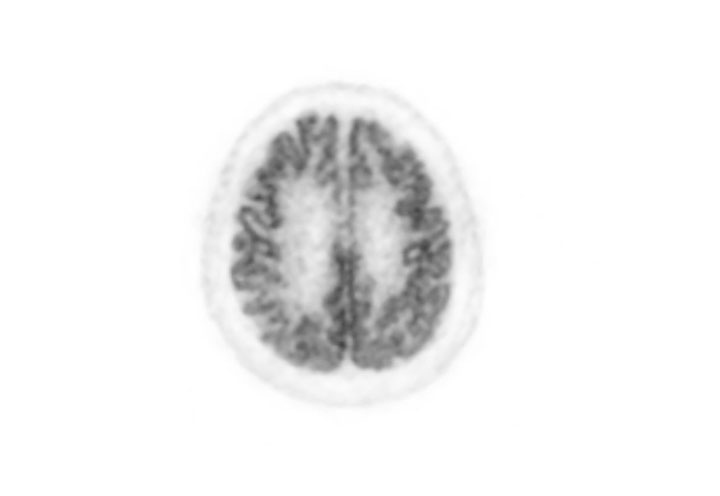

Head / Case2 : FDG

Courtesy : Kindai University Hospital

- Imaging protocol

- Injected dose: 3.29 MBq/kg, 18F-FDG

- Uptake time: 38 minutes

- Scan time: 30 minutes